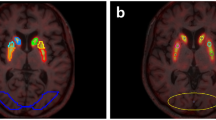

Participant characteristics are shown in Table 1. Relative tracer delivery measures (R1) are reported in Table 2, with a significantly lower global R1 in AD dementia patients compared with CU participants, for both test and retest scans (p < 0.01).

LME analyses showed that test and retest R1 values were strongly correlated and that the slope was not significantly different from 1 (R2=0.92, slope=0.98 C.I. [0.94–1.01], p<0.001). Furthermore, amyloid status as measured by visual read did not have a significant effect on this relationship. Finally, Bland-Altman analysis showed a negligible bias (0.69±3.07 %) between test and retest R1 (Fig. 1). All analyses were also carried out using RPM-derived R1 which resulted in essentially identical results (data not shown).

Differences in R1 between diagnostic groups were as expected, with lower average R1 values in AD dementia patients compared with CU participants. This finding is in agreement with existing literature where decreases in (relative) perfusion related to AD pathology have been reported for both R1 and [15O]H2O PET studies [3, 23, 24]. Furthermore, by incorporating these two groups, the present study covered the entire range of R1 values that would be expected in clinical studies across the AD spectrum.